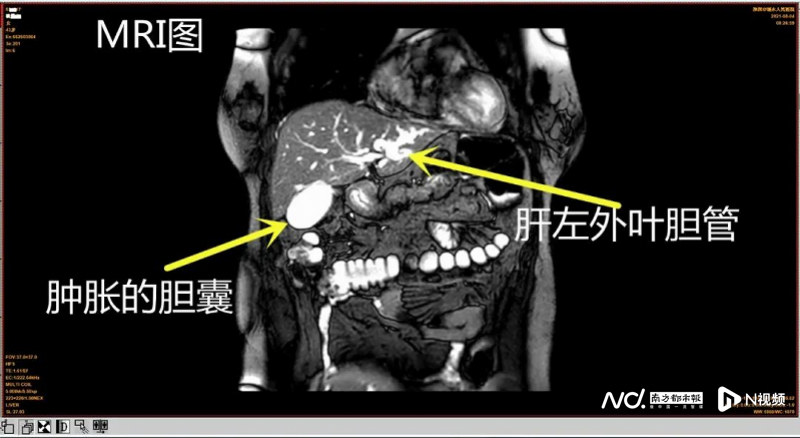

结合病史,经诊断,倪女士为急性梗阻性化脓性胆管炎、肝内外胆管结石、胆囊结石和肝左叶萎缩,病情凶险且严重。

紧接着,宋主任率领团队为患者急诊进行了胆囊切除术,肝左外叶切除术,肝二,三段胆管及胆总管切开,联合胆道镜肝内外胆管取石,T管引流术。约半个月后出院。